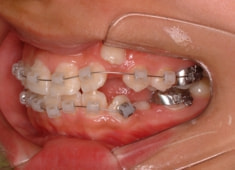

治療開始時

治療開始から5ヶ月後